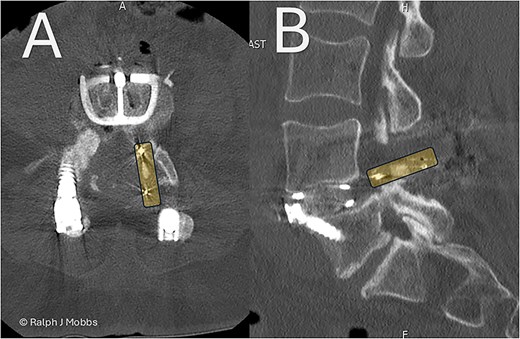

This case report illustrates a novel two-stage revision strategy for symptomatic L4/5 pseudarthrosis (Fig. 1A), integrating anterior lumbar interbody fusion (ALIF) with posterior endoscopic cage retrieval and decompression. The initial ALIF procedure (Fig. 1B) enabled restoration of segmental lordosis, disc height, and immediate biomechanical stability, while also facilitating distraction of scarred posterior elements. This was followed by a targeted, minimally invasive endoscopic procedure to remove the failed TLIF cage and decompress neural elements (Video 1), thereby avoiding the morbidity of an open posterior revision.

(A) Initial presentation with TLIF cage migration posteriorly into the spinal canal and paraspinal muscles. (B) Stage 1 and 2 completion, including revision fusion using an ALIF cage (Redmond Ti/PEEK, A-spine, Taiwan) and TLIF cage removal. (C) CT scan post TLIF removal and disc height restoration with ALIF cage.

A 64-year-old female with a history of a TLIF at L4/5, performed 18 months prior to presentation to the current surgeon, presented with persistent low back pain and radiculopathy. Imaging demonstrated non-union at the TLIF site with ongoing foraminal stenosis and segmental instability (Fig. 1A). Multidisciplinary review determined that a revision fusion was the initial focus as mechanical back pain related to non-union was the primary complaint. Following the planned stage 1 intervention, removal of the migrated TLIF cage was determined necessary as the device was serving no purpose and likely causing further symptoms. Therefore, a two-stage revision strategy was planned.